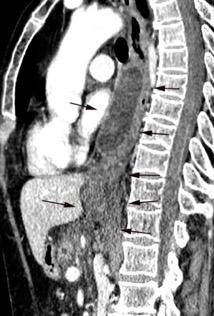

Diafragma “colgante” (“dangling sign”)

(“Dangling sign”)

TC. Mejor con multicorte. (reconstrucciones).

Asociación: Aire en pared.

Fracturas costal .Rotura esplénica. Neumoperitoneo.

Diafragma discontinúo Herniación de la grasa omental

Desser TS et al.The dangling diaphragm sign: sensitivity and comparison with existing CT signs of blunt traumatic diaphragmatic rupture. Emerg Radiol 2010